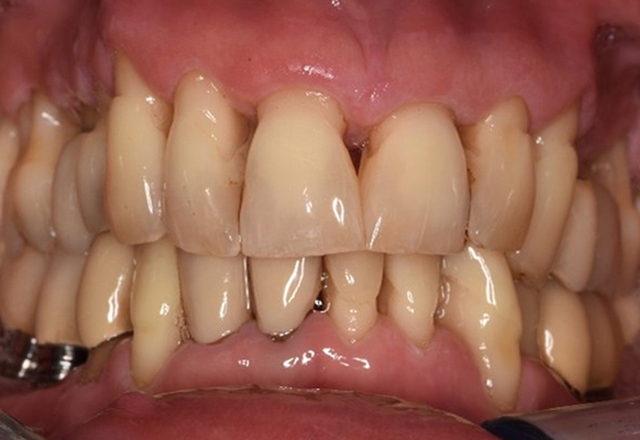

Patientenfälle nach IPCUm das Zusammenspiel der für den IPC definierten Bedarfs- und Risikofaktoren sowie die Auswirkungen einzelner Faktoren zu illustrieren, dienen nachstehende Fallbeispiele*. Die mundgesunde DiabetikerinEine 51-jährige mundgesunde Diabetikerin stellt sich zur Präventionssitzung vor. Die Blutzuckerwerte sind stabil bei einem HbA1c = 6,2%, folglich gilt sie mit dem entsprechenden Medikament Metformin (Antidiabetikum) als suffizient eingestellt. Die Patientin hat keine bestehenden Versorgungen oder orale Vorerkrankungen. Anhand der aktuellen Befunde lässt sich eine Gingivitis bei sonst stabilem parodontalem Zustand (Stage II, Grad B) feststellen. mehr Infos Fallpräsentation: Management komplexer ZahnprothetikEs ist längst bekannt, dass Mundgesundheit und Allgemeingesundheit in direktem Zusammenhang stehen und einen zum Teil bidirektionalen Einfluss aufeinander haben. Die Berücksichtigung beider Faktoren sind bei der Planung der oralen Prävention und Therapie der Patienten in der Zahnarztpraxis unabdingbar. Dabei ist oberstes Ziel, die Gesundheit und die Lebensqualität der Patienten sowohl aus zahnmedizinischer -und medizinischer Sicht zu erhalten. mehr Infos Der (mund)-gesunde Patient mit ImplantatenDer 55-jährige Patient gibt in der Anamnese an, keine Allgemeinerkrankungen zu haben und keine Medikamente einzunehmen. Die Lebensgewohnheiten des Patienten sind ebenfalls unauffällig. Der Patient hat einige zahnärztliche Restaurationen und zwei Implantate (2. und 4. Quadrant). Anhand der aktuellen Befunde lässt sich eine Gingivitis bei stabilem parodontalen Zustand am reduzierten Parodont (Stadium III, Grad A) feststellen. mehr Infos Der gesunde Patient mit parodontaler Vorerkrankung & PeriimplantitisEin 52-jähriger Patient stellt sich zur Präventionssitzung vor. Der Patient hat keine Allgemeinerkrankungen und nimmt keine Medikamente ein. Er hat verschiedene zahnärztliche Versorgungen und zudem zwei aktive kariöse Läsionen. Außerdem verfügt der Patient über vier Implantate (2., 3. und 4. Quadrant). Es zeigt sich eine parodontale Vorerkrankung (Stadium IV, Grad B). Derzeit herrschen stabile parodontale Verhältnisse, lediglich am Implantat regio 36 zeigen sich Sondierungstiefen (ST) von 5 mm. Zudem lässt sich eine Gingivitis feststellen. mehr Infos Der Diabetiker mit ParodontitisDieser Fallbericht eines 52-jährigen Mannes mit Typ-2-Diabetes und Parodontitis hebt hervor, wie durch individuelle Vorsorgemaßnahmen, die Gesundheit des Zahnhalteapparates erhalten bzw. das Fortschreiten der Erkrankung kontrolliert werden kann. mehr Infos Der 28-jährige Raucher mit ZahnerosionenDieser Fallbericht eines 28-jährigen Rauchers mit Zahnerosionen zeigt die Bedeutung personalisierter Patientenprofile. Er unterstreicht die Notwendigkeit, sowohl die Mundgesundheit als auch die allgemeine Gesundheit zu berücksichtigen, um Erkrankungen der Zähne bzw. des Zahnhalteapparates effektiv zu verhindern. mehr Infos Der Endokarditis-Patient mit aktiven KariesläsionenDer Patient ist 39 Jahre mit Z.n. Herzklappenersatz wegen Klappenfehlers und Endokarditis. Als Antikoagulans (Gerinnungshemmer) wird regelmäßig ASS 100 eingenommen. Aus dem Bereich Lebensstil ist die Ernährungsweise als kariesfördernd einzustufen, da mit hoher Regelmäßigkeit zuckerhaltige Lebensmittel sowie sechs bis sieben Mahlzeiten täglich verzehrt werden. Die Mundgesundheit des Patienten zeigt ein mittleres Kariesrisiko mit aktiven Läsionen. Das Parodontitisrisiko ist niedrig, es besteht eine Gingivitis. Es ergeben sich folgende Empfehlungen für die Prophylaxebehandlung. mehr Infos Die gesunde Patientin mit parodontaler VorerkrankungDie 68-jährige Patientin hat keine zahnmedizinisch relevanten allgemeingesundheitlichen Vorerkrankungen oder Medikation, auch aus dem Lebensstil ergibt sich kein besonderes Risiko. Die Patientin hat zwei Implantate (3. Quadrant, seit fünf Jahren) sowie eine parodontale Vorerkrankung (Parodontitis Stadium IV, Grad B) mit Zahnverlust. Derzeit zeigen sich stabile parodontale Verhältnisse. Für die Prophylaxesitzung ergeben sich vier Empfehlungen in den Bereichen Anamnese/Befund, Motivation/Instruktion, der Wahl der geeigneten Instrumente und für Resümee/Folgetermin. mehr Infos